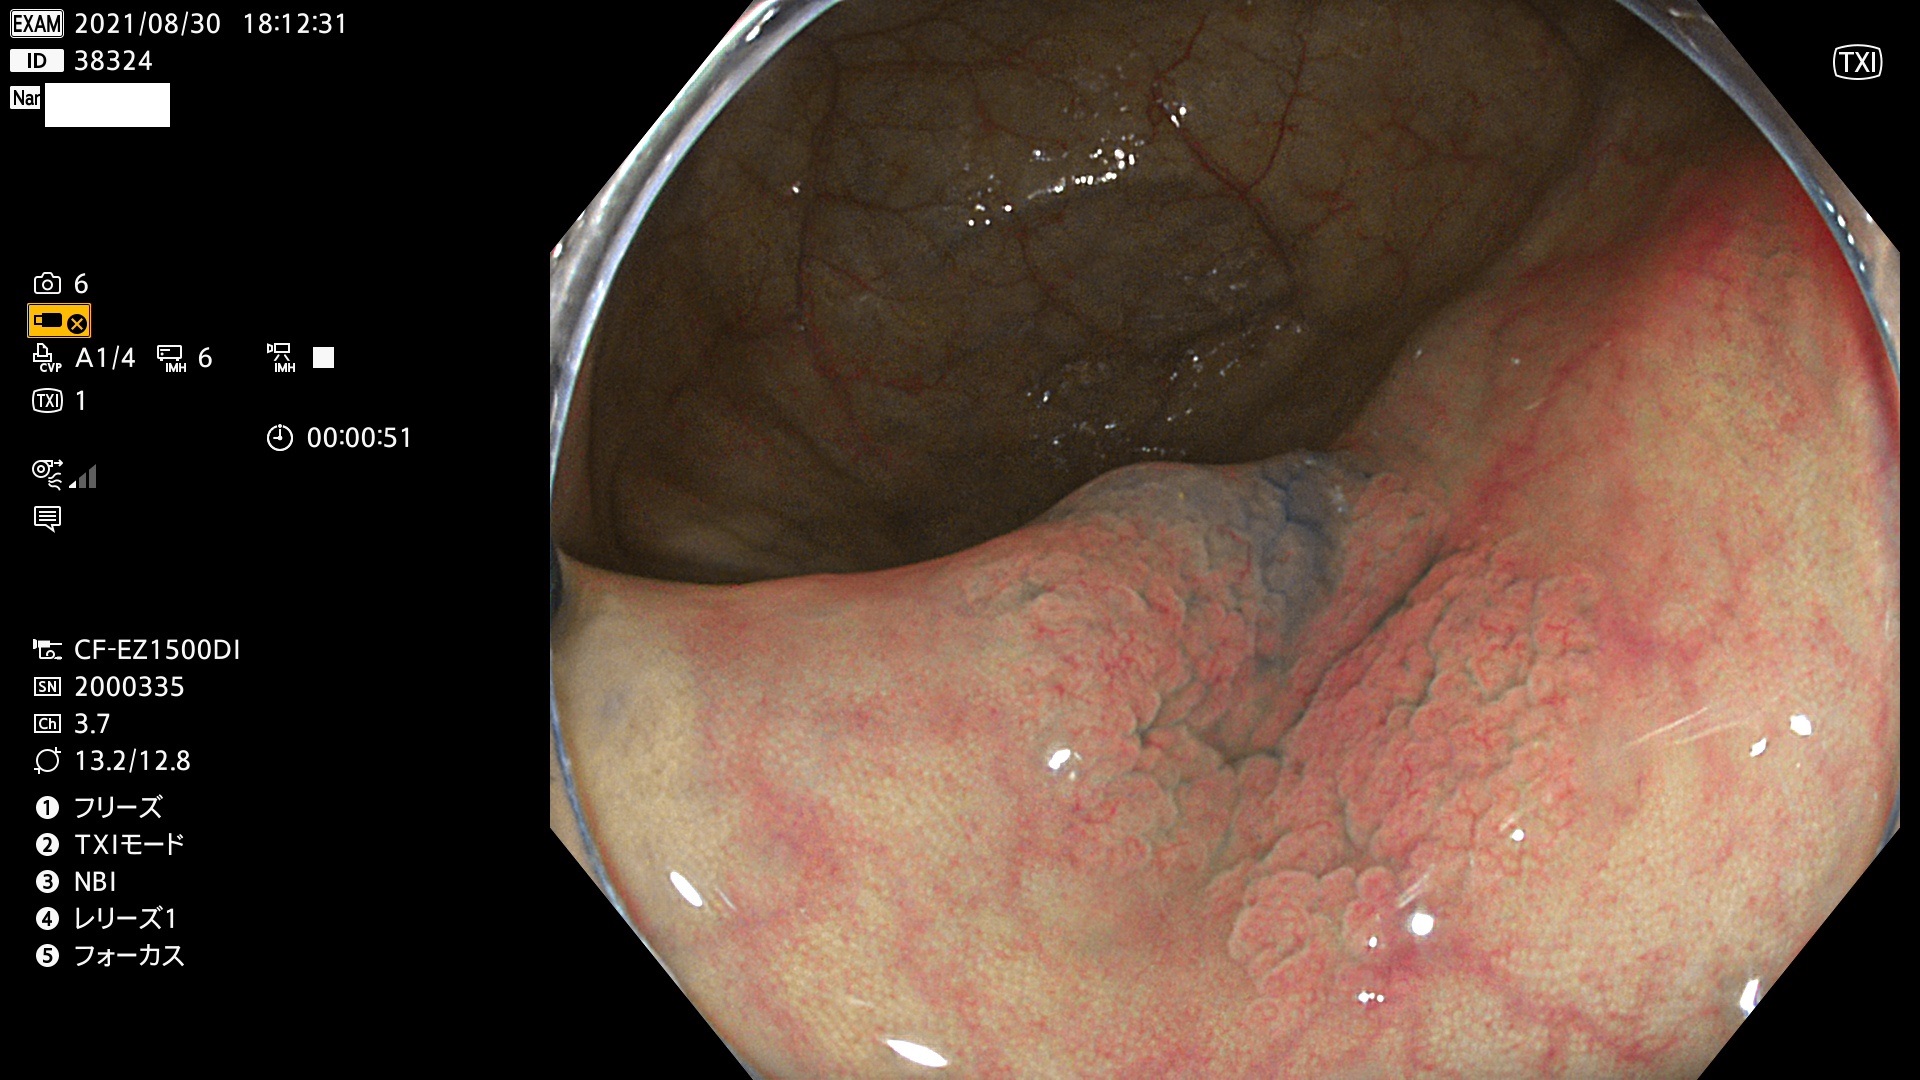

38300 38301 38302 38303 38304 38306 38307 38308 38309 38310 38311 38312 38313 38314 38315 38316 38317 38319 38321 38322 38323 38324 38325 38327 38331 38332 38333 38334 38337 38338 38339 38340 38341 38343 38346 38348 38349 38350 38351 38352 38353 38354 38355 38358 38359 38360 38361 38362 38363 38365 38366(SSAP) 38368 38369 38370 38371(SSAP) 38372 38374 38375 38376 38377 38378 38380 38381 38382 38383 38384 38385 38386 38388 38389 38391(SSAP) 38395 38397 38399

発見困難で危険性の高い平坦型病変(上記100名より抽出)